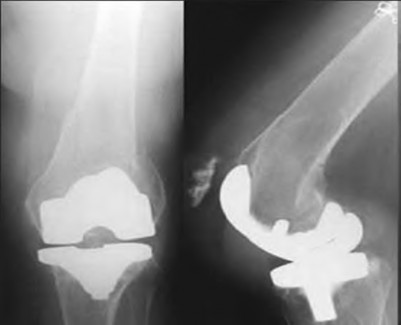

A 60-year-old male tennis player undergoes a unicompartmental knee arthroplasty (UKA) shown in Figures A and B. Which of the following statements regarding this procedure is true?

Figures A and B depict radiographs of a unicompartmental knee arthroplasty (UKA). UKA kinematics have been shown to most closely approximate native knee kinematics.

In an in vitro cadaver study, Patil et al found that TKA significantly changed knee kinematics while the unicompartmental replacement preserved normal knee kinematics.

Fisher et al performed a retrospective study comparing the short-term outcomes of small-incision unicompartmental knee arthroplasty (UKA) with standard total knee arthroplasty (TKA) in 91 consecutive patients older than 70 years. They found: 1) Blood loss was significantly more for the TKA group, as was the need for blood transfusion. 2) Patients with unicompartmental replacements had a much quicker return of function and discontinuation of pain medication. 3) While knee scores and ROM were similar preoperatively, both were better in the unicompartmental group at each postoperative time interval. 4) Narcotic use and length of hospital stay were also significantly less for the unicompartmental group. Therefore answers 2,3,4 and 5 are false.